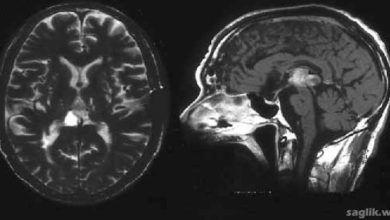

Astrositom Nedir? Belirtileri, Nedenleri, Tedavisi

Astrositom (astrocytoma), yaygın bir beyin tümörü türüdür. Astrositom beyin tümörü, sinir hücrelerini destekleyen astrositler adı verilen hücrelerde başlar. Astrositom belirti…